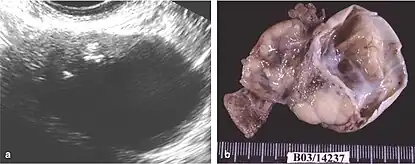

Benign mixed Brenner tumor and mucinous cystadenoma of the right ovary. (a) Transvaginal ultrasound images show mixed cystic and solid components, with calcifications in the solid portion (arrow); (b) Macroscopic evaluation revealed an ovary partially replaced by a solid and cystic tumor[2]

Brenner tumors (BT) are infrequent ovarian growths composed of specialized ovarian cells surrounded by dense fibrous tissue. Typically small (less than 2 cm), these tumors are often discovered incidentally in women without apparent symptoms.[2] However, when a BT is borderline or malignant, indicating a potential for cancer, it may lead to symptoms such as an abdominal lump, abdominal pain, and post-menopausal bleeding. Less common signs include nausea, vomiting, back pain, bowel problems, reduced appetite, and weight loss.

Differentiating between benign (non-cancerous) and malignant (potentially cancerous) BTs poses a challenge as they appear similarly in medical images.[13] The definitive diagnosis involves examining tissue under a microscope (histopathology). Benign BTs exhibit a consistent fibrous structure, a distinctive characteristic. They may also manifest as a cystic mass with multiple compartments, particularly associated with other ovarian growths.[14]